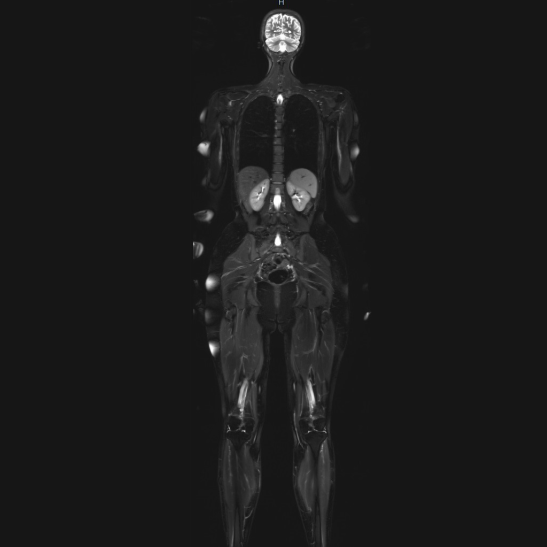

Wir bieten Ihnen eine Auswahl moderner, strahlenfreier Vorsorgeuntersuchungen an, die individuell auf Ihr persönliches Risikoprofil zugeschnitten werden. Besonders empfehlenswert sind präventive Untersuchungen für Menschen mit familiärer Vorbelastung oder als regelmäßiger Bestandteil der Gesundheitsvorsorge.

Unsere Präventionsuntersuchungen im Überblick